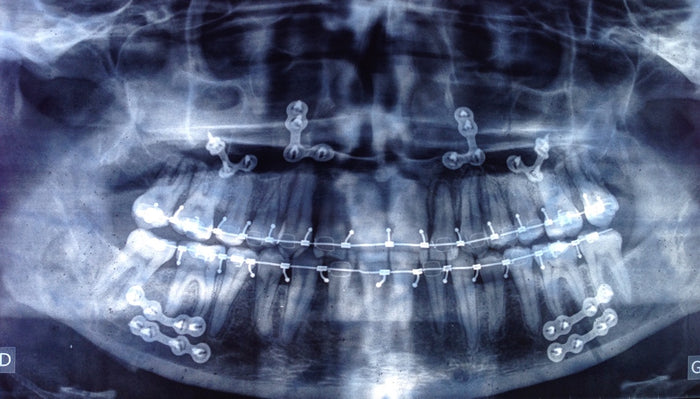

Faut-il retirer les plaques d’ostéosynthèse après la chirurgie maxillo-faciale ?

- Vanessa Perrin, a subi une chirurgie bi-maxillaire.